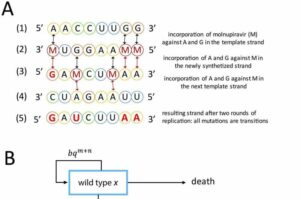

SARS-CoV-2: Molnupiravir potrebbe generare un super-virus?

SARS-CoV-2-Immagine: la sicurezza evolutiva della mutagenesi letale guidata dal trattamento antivirale. Credito: PLOS Biologia (2023)- Ai pazienti affetti da COVID-19 vengono spesso…